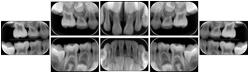

OO.1.2 Ophthalmology

1. A patient in rural Canada visits a general ophthalmologist and is found to have diabetic macular edema. The general ophthalmologist would like to discuss the case with a retina specialist before performing laser surgery. A fluorescein angiogram is done with multiple retinal images taken in a timed series after an intravenous injection. The images along with a Structured Display are shared via a Health Information Exchange with a retina specialist in Calgary, who opens them using his Ophthalmology EMR software and consults via phone with the general ophthalmologist. Both physicians view the images in the same layout so the retina specialist can provide accurate guidance for treating the patient.

2. A patient in rural Iowa visits his primary care physician for management of diabetes. Three non-mydriatic (patient's eyes are not dilated) photographs are taken of the back of each eye, and forwarded electronically along with a Structured Display to an ophthalmologist in Iowa City. The ophthalmologist reads the photos in an agreed upon layout so there is no mistake about what portion of which eye is being viewed. The ophthalmologist is able to tell the primary care physician that his patient does not need to come to Iowa City for face to face ophthalmologic care, but that there is a particular view of the left eye that should be photographed again in 6 months.

Ophthalmic Retinal Study Structured Display

Figure OO-3. Ophthalmic Retinal Study Structured Display